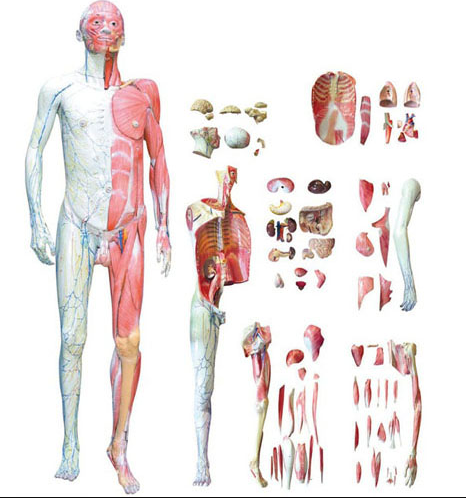

■ 尺寸:自然大,400×260×80mm;

■ 部件:1部件,置於底座上;

■ 功能:模型示約第三胸椎高度示斷麵結構,按正常解(jiě)剖姿(zī)態平下縱隔(gé)作一橫(héng)切,示肺裂,肺部的動(dòng)脈、靜脈(mò)、支氣管的斷麵關係(xì)、胸膜、肋間肌及前側(cè)、左右側胸廓肌肉,同時還可示脊柱、脊髓通過此平麵的結構、毗鄰關係(xì)等,前方示(shì)左右心房、心室等;

■ 材質(zhì):進口環保PVC材料,進(jìn)口環保油漆。